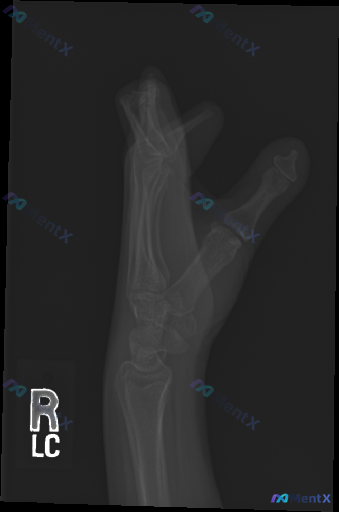

各位同道,今天分享一张手部侧位X光片。影像所见:手部呈屈曲(握拳)位投照,掌骨(第2-5掌骨)及指骨(近节、中节、远节)形态大致完整,骨结构尚连续,骨小梁纹理清晰,骨密度未见明显异常增高或减低,未见明显皮质连续性中断、骨折线或透亮线,未见明显溶骨性或成骨性病变征象;掌指关节、指间关节对位关系可见,关...